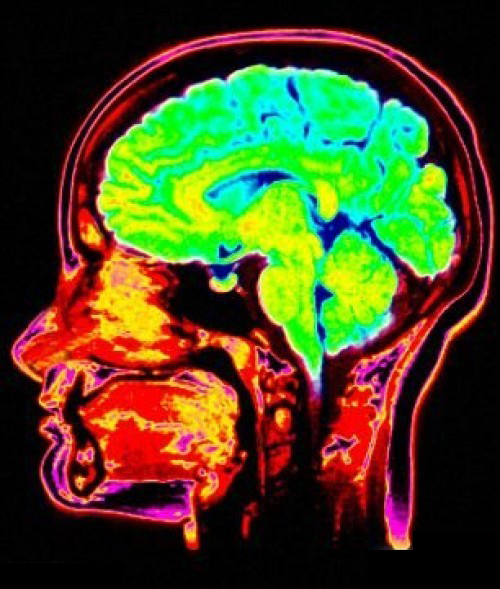

新的研究指出帕金森病患者認(rèn)知障礙與大腦多個(gè)區(qū)域的神經(jīng)元缺失有關(guān)。通過(guò)大腦成像技術(shù),研究發(fā)現(xiàn)導(dǎo)致帕金森病運(yùn)動(dòng)障礙的大腦區(qū)域變化也會(huì)造成輕微的認(rèn)知障礙。在嚴(yán)重認(rèn)知障礙的帕金森病患者中,大腦不同區(qū)域的變化起到的作用也大不相同。這篇文章發(fā)表在2014年12月15日的JAMA Neurology雜志上。

帕金森病的運(yùn)動(dòng)癥狀是由一個(gè)名叫黑質(zhì)的大腦區(qū)域中的神經(jīng)元消亡引起的,這些神經(jīng)元負(fù)責(zé)與紋狀體中的神經(jīng)元進(jìn)行通訊。紋狀體是大腦的另一個(gè)區(qū)域,負(fù)責(zé)控制我們的運(yùn)動(dòng)。但是帕金森病導(dǎo)致人腦產(chǎn)生認(rèn)知障礙的原因還未明確。阿爾茲海默癥(老年癡呆)由于類膽堿能神經(jīng)元導(dǎo)致,那么多巴胺神經(jīng)元是導(dǎo)致帕金森病患者的認(rèn)知障礙的元兇嗎?研究人員一直對(duì)它高度懷疑。

密西根大學(xué)的尼古拉斯.布恩(NicolaasBohnen)博士利用大腦成像技術(shù),對(duì)143位帕金森病患者進(jìn)行了檢查,他們大多數(shù)都沒有癡呆。這些受試者根據(jù)認(rèn)知障礙的嚴(yán)重程度被分為5組,這樣他們的大腦影像才具有對(duì)比性。